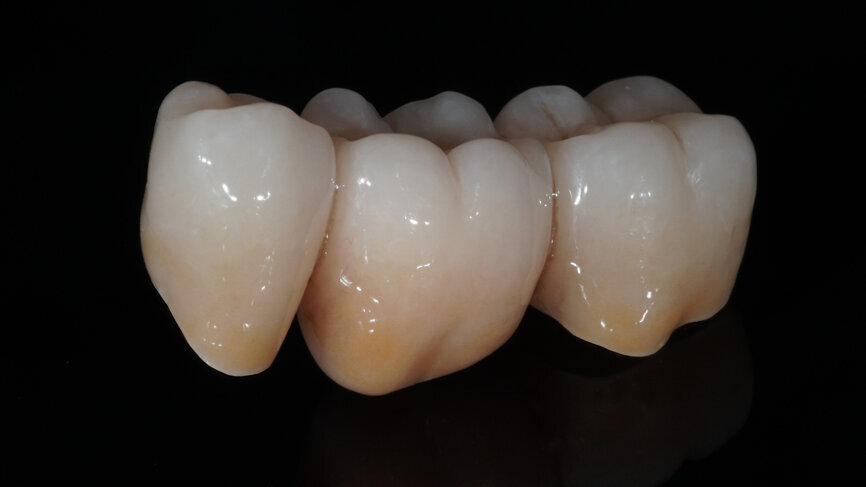

Fig. 9: Appearance of the bridge after individualisation with CERABIEN ZR FC Paste Stain.

Fig. 10: Appearance of the bridge after two glaze firings.

One week later, the extraction socket, which was still healing, was modelled for the ovoid pontic using an electrotome loop. The second premolar and molar were prepared as abutment teeth for a bridge. The bridge was then designed (Figs. 4–6) and milled from KATANA Zirconia Block for Bridge in Shade A3.5 and individualised with CERABIEN ZR FC Paste Stain (both Kuraray Noritake Dental; Figs. 7–10). A further week later, the bridge was luted with the self-adhesive resin cement PANAVIA SA Cement Universal after sandblasting (Figs. 11–13).